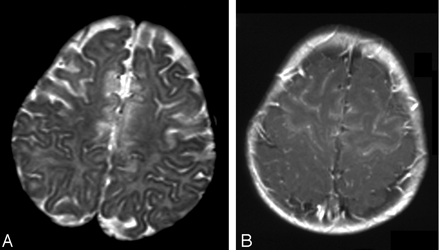

Patient 2. Axial T2-weighted images.

A, At presentation, large area of hyperintensity is present in the pons.

B, Involvement of the frontal region, up to the motor cortex, is extensive.